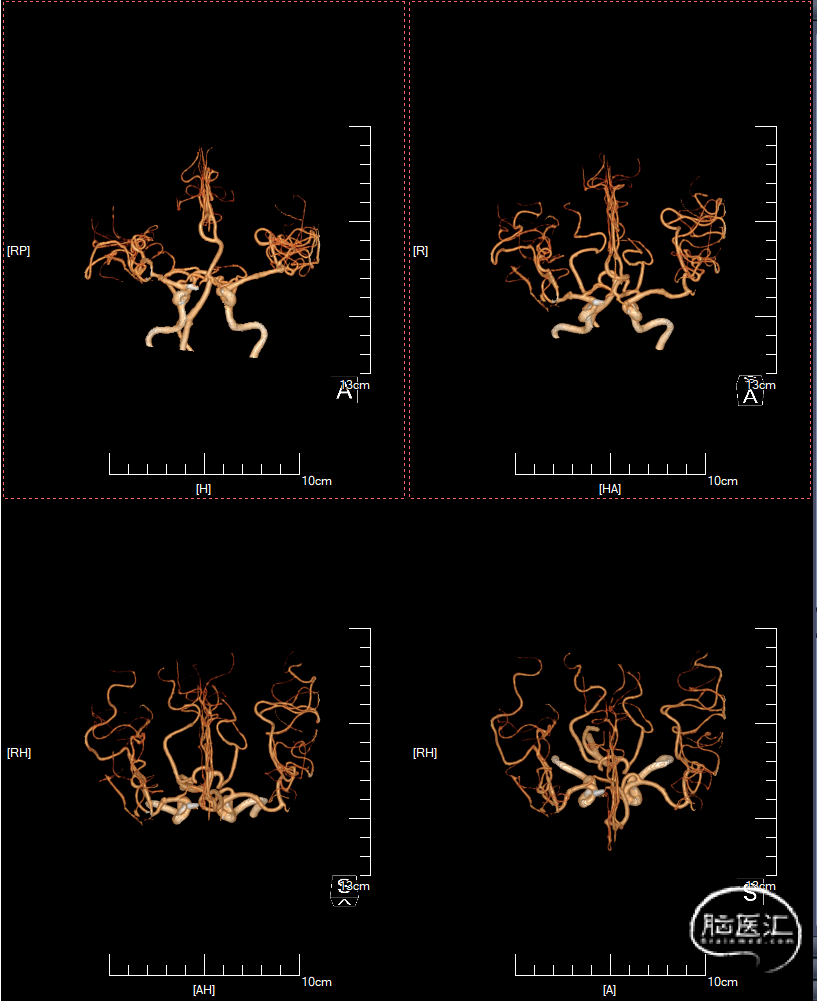

入院后行DSA检查,显示右侧颈内C6-7段动脉瘤右侧大脑中动脉M1分叉动脉瘤。

C6-7段动脉瘤位于颈内动脉上壁,指向内上方,考虑血泡样动脉瘤,结合蛛血位置,及动脉瘤形态、大小,考虑颈内动脉血泡为责任动脉瘤。